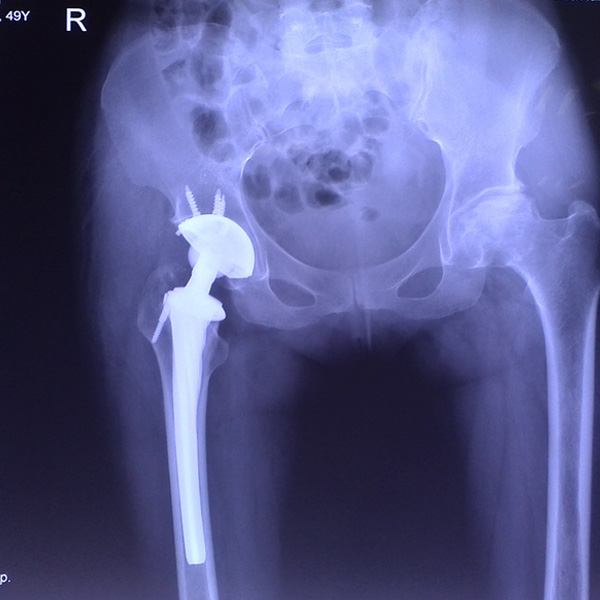

髖關(guān)節(jié)翻修

患者蘇某,女性,11年前因“左髖關(guān)節(jié)屈曲攣縮畸形”行左側(cè)人工全髖關(guān)節(jié)置換,近來感覺左髖關(guān)節(jié)疼痛,不敢行走,經(jīng)“攜生醫(yī)療平臺”就診于哈......